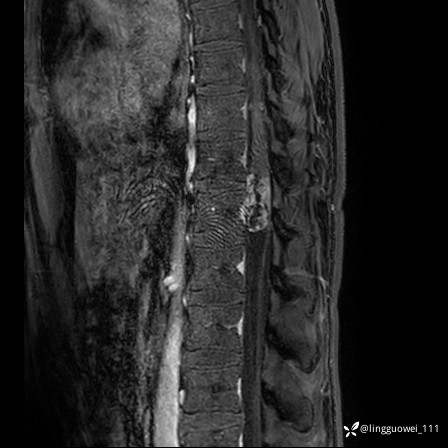

男,38岁,反复腰痛伴双腹股沟区痹痛半年,加重1月。

腰椎MR,注意脊髓异常信号,与伪影鉴别,一不小心就会漏诊

T1WI: